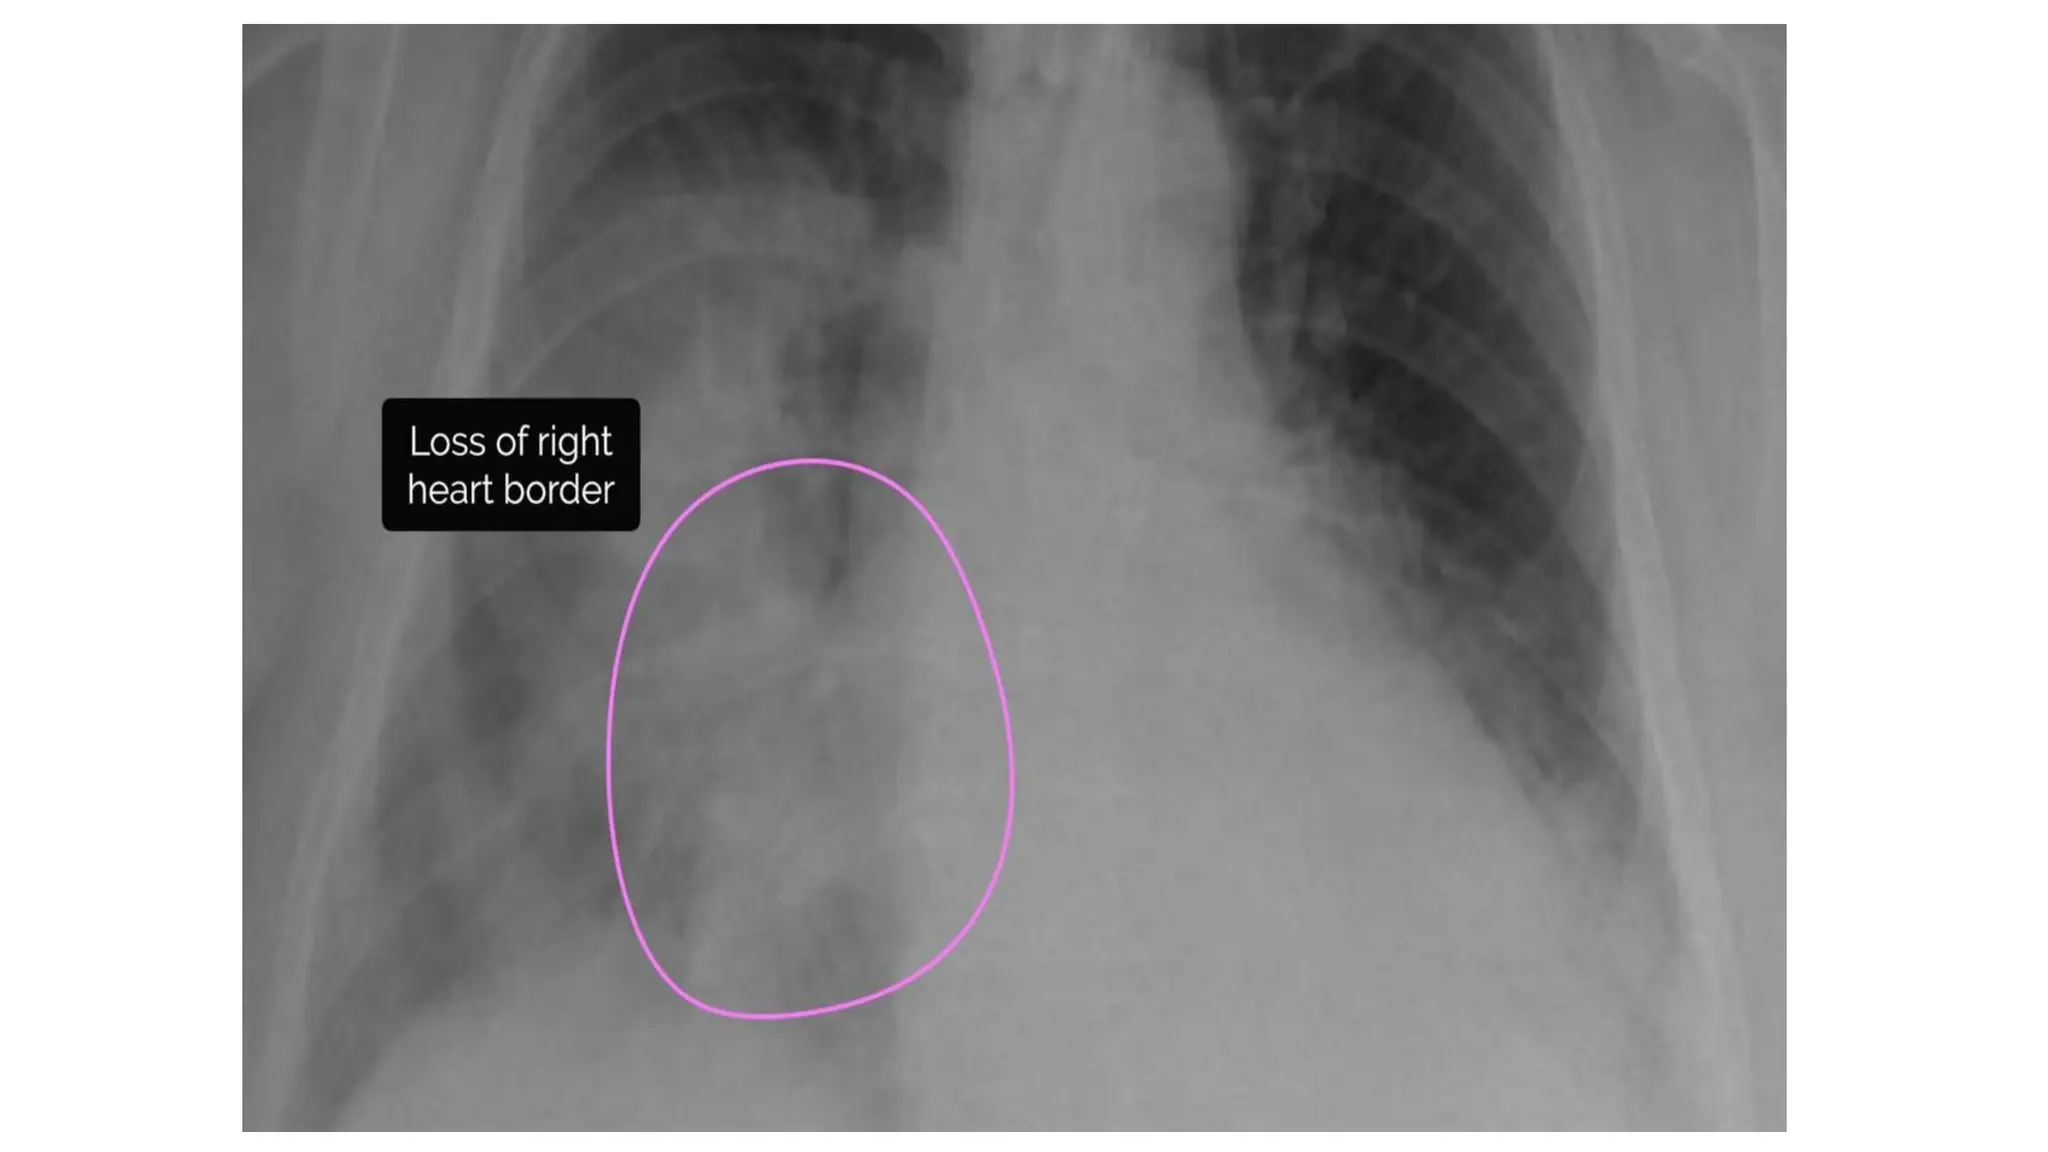

Cardiac borders

• In healthy individuals the borders

of the heart should be clearly

visible & well-defined.